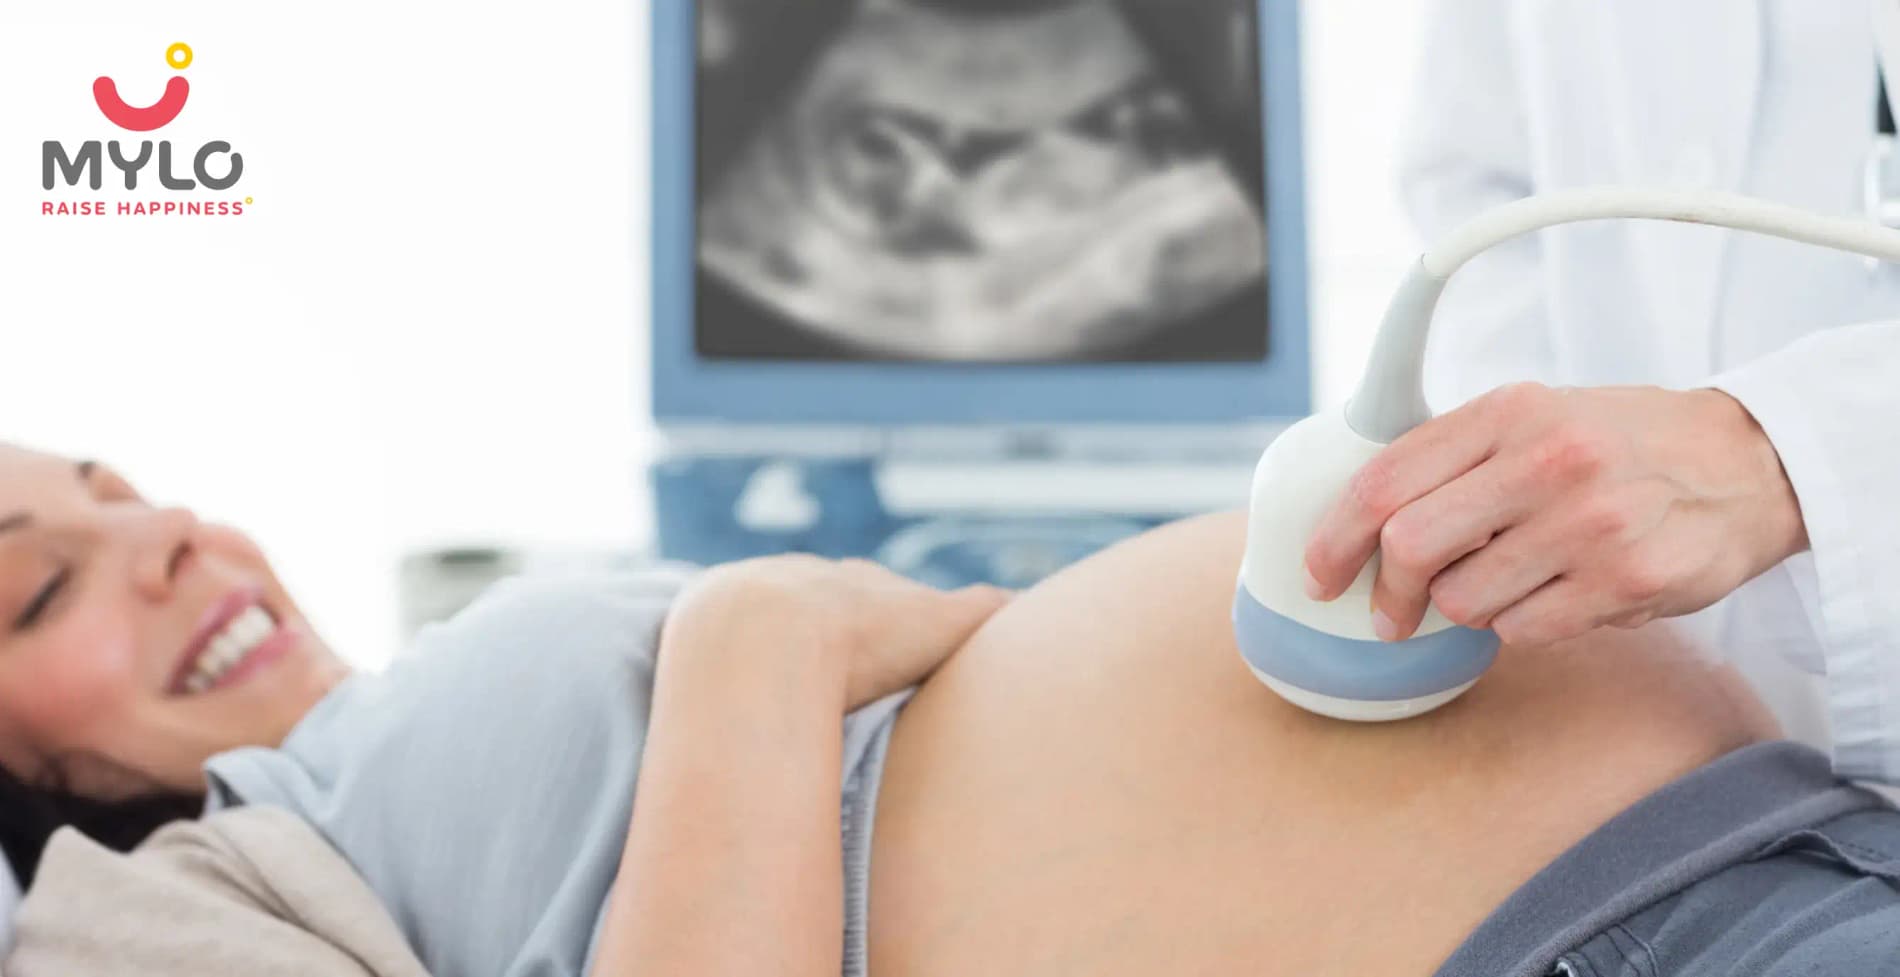

Scan & Tests can confirm your pregnancy and also monitor your baby’s development in the womb